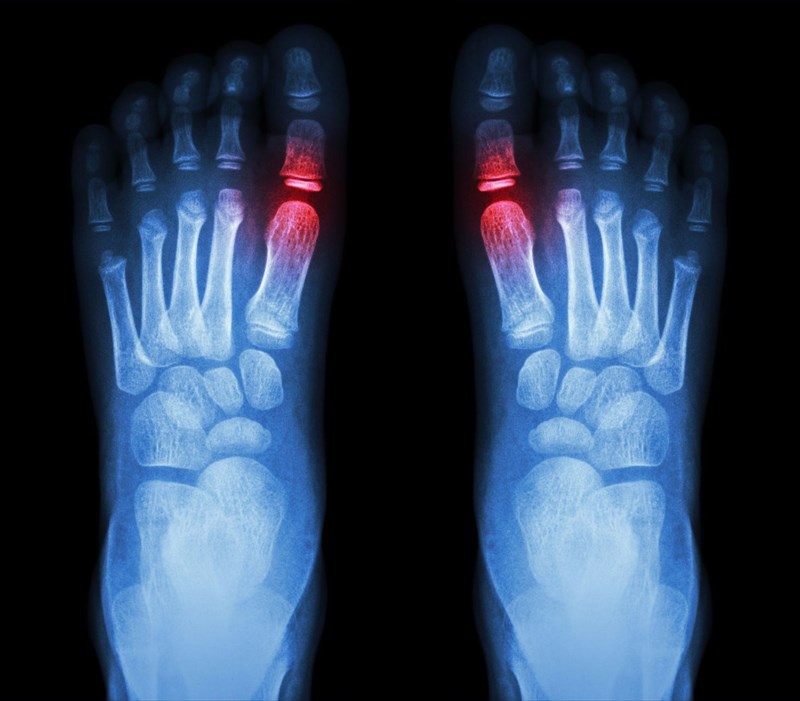

• Imaging tests: A doctor may also recommend imaging tests to check for urate crystal formations. Options include X-rays of the affected joint/s which can clearly indicate signs of inflammation, a musculoskeletal ultrasound, or dual energy CT (computerised tomography) scan, which can pick up crystal formation even if the affected area is not inflamed. Imaging tests can also help to determine any potential damage to joints and tissues affected by gout flares.